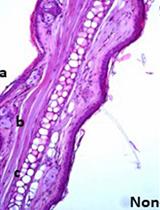

Graphical representation comparing modified RNA isolation protocols for efficient RNA extraction from guinea pig cartilage and synovium